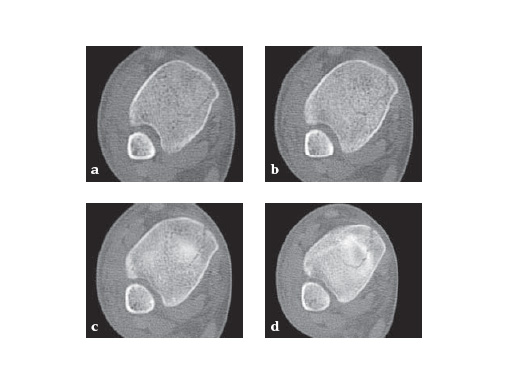

29-year-old female after a motor vehicel crash

Case provided by Sean Nork, Washington, USA

The fibula was reduced and stabilized through a posterolateral surgical approach. A small anterior incision was used to apply multiple clamps and to access the fracture reduction. A medial locked distal tibial plate was placed adjacent to the anteromedial surface of the tibia through a 4 cm distal incision. Multiple proximal screws were placed through small incisions overlying the plate.